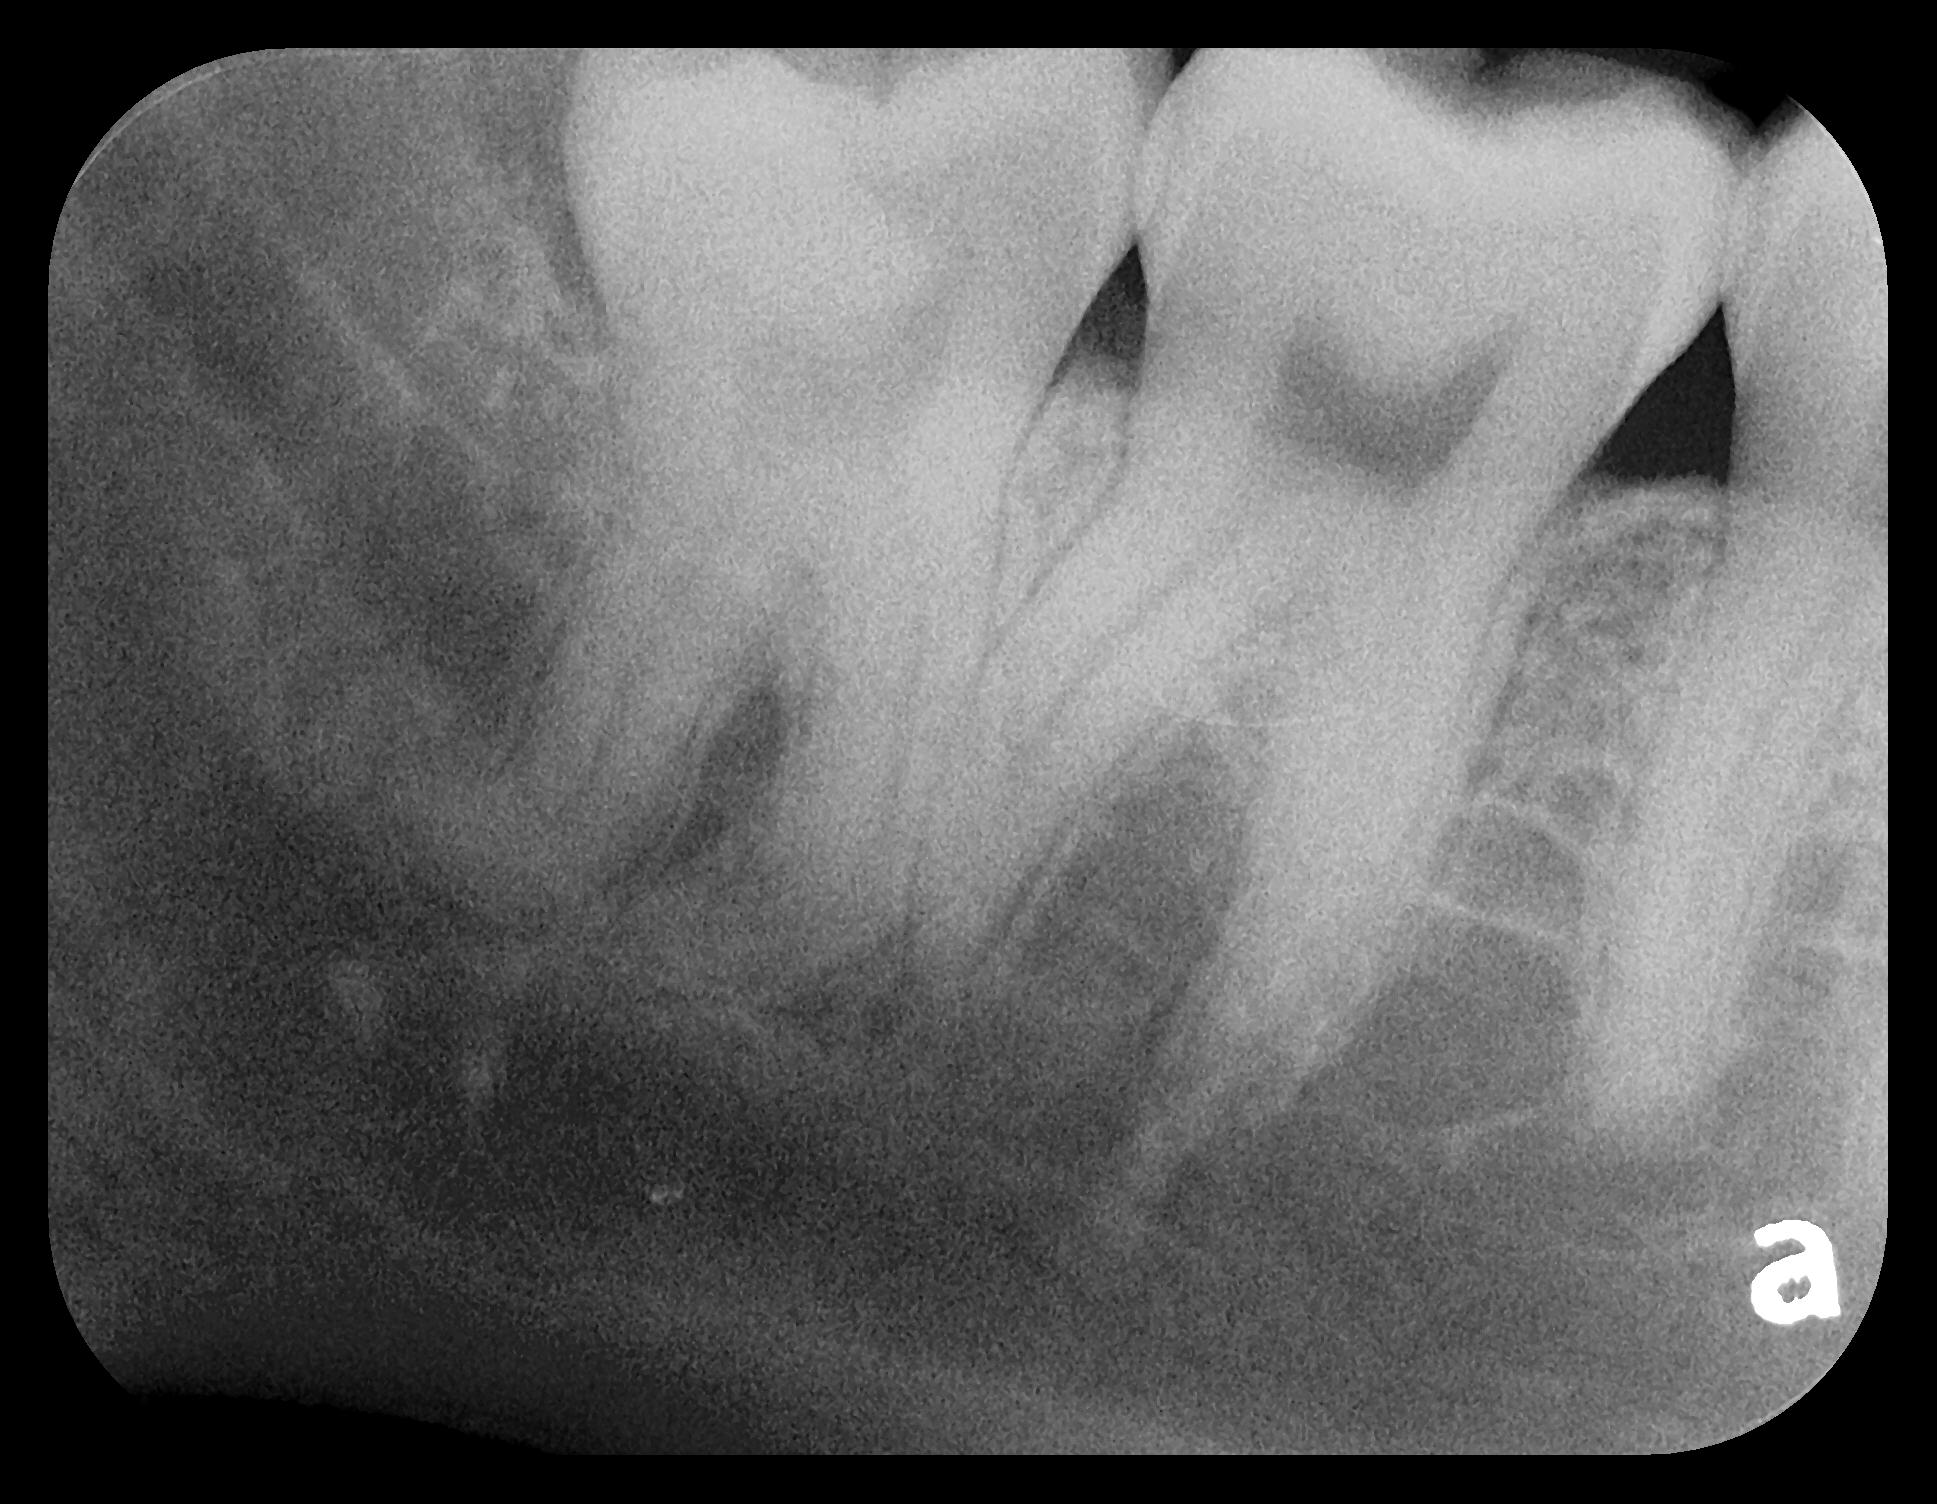

Some representative radiographic PSP images are exhibited here for demonstration of the anatomy and pathology that can be visualized with this technology. Many of these images would not have been possible if HW technology were used (Figure 3 through Figure 8).

As displayed here, the 2D radiographic images in Figure 3 through Figure 8 can alert the clinician to the need for a further 3D CBCT analysis to properly ascertain the anatomy and extent of the pathology that is initially visible in the intraoral radiographs. Proper treatment or referral to the appropriate specialty practice can follow.5,6 No. 2 PSP radiographs, when used in a conventional full-mouth series of radiographs on a patient with a relatively complete dentition, will routinely allow visualization of the anatomy of third molars, mandibular canal, maxillary sinuses, full dental root morphology, and bone anatomy beyond the apices2,16,17 (Figure 9 and Figure 10).

Fig 3. Two PSP PA radiographs of mandibular teeth showing: left, the initial view

of molar area and suspected pathology surrounding impacted tooth No. 32; center,

subsequently exposed PA radiograph, placed more distally, demonstrates extent

of large cyst as well as entire tooth and root No. 32. Proper alert as to presence

of suspected cyst and appropriate referral for 3D CBCT study and surgical

enucleation was given to the patient. Right: Same radiograph as on the left, but

with lighter superimposed outline of the area that would be visible using an HW

sensor rather than a PSP sensor. The small area of pathology is likely obscured

because it is visually overlaid by the root of tooth No. 31. Neglect of this significant

pathology may have resulted.

Figure 3